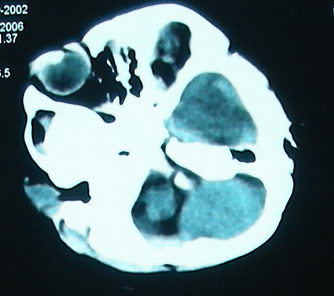

左侧大脑半球和右侧额叶大片低密度影,脑沟及外侧裂池消失,左侧脑室闭合,考虑脑梗塞伴有水肿。

考虑:1、左额颞顶慢性硬膜下血肿(可能为产伤所致);

2、蛛网膜下腔出血;

3、左侧大脑半球及右额叶脑肿胀、梗塞(缺血性脑梗塞为脑疝所致)。

病人预后会很差。

结合临床考虑1、脓毒栓子致左侧大脑半球及右侧额叶梗塞。2、左侧额颞顶部硬膜下血肿形成.3、镰下疝形成。

左侧大脑半球和右侧额叶大片低密度影,脑沟及外侧裂池消失,左侧脑室闭塞,左侧蛛网膜下腔片絮状高密度影,结合病儿高热、脑膜刺激征(+),考虑:炎脑,脑水肿,左侧蛛网膜下腔出血。至于出血原因,应该为高热所致维生素c需要量增加,而补给不足所致维生素c缺乏,抑或是使用抗惊厥药影响维生素k代谢,使凝血发生障碍而出血。当然,一切都是猜测,需要临床进一步检查验证。

1、左额颞顶慢性硬膜下血肿;